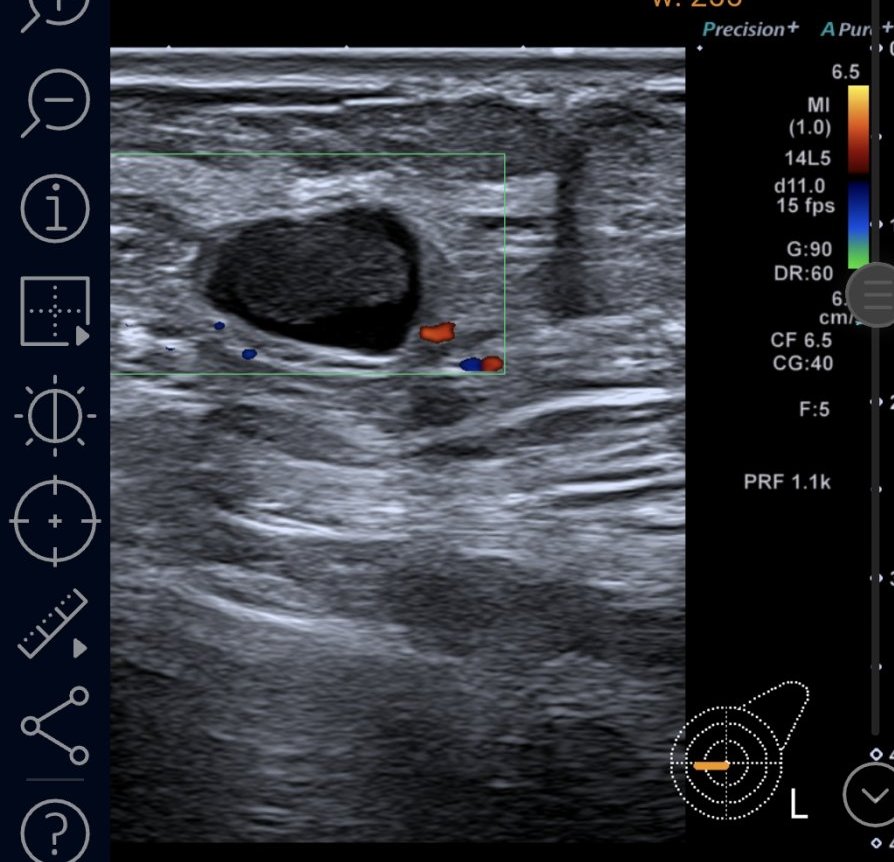

Далинда, ето малко картинки от BIRADS 4c ( най- вече вляво) , само по образни. Това са първите картинки, оттогава имам още нови попълнения. Биопсията не показа точно какво е и какво не е, според лекарите може би не са "уцелили" точното място в лезията, защото има известно разминаване. Вчера бях на ПЕТ, само сумтяха и ми казаха, че ще разбера резултатите от лекуващата другата седмица, след като е минала Туморната комисия 🤷‍♀️

Marie curie, твоето само по формата и е силно подозрително за рак. Неправилни, наръбени форми са червена лампа.